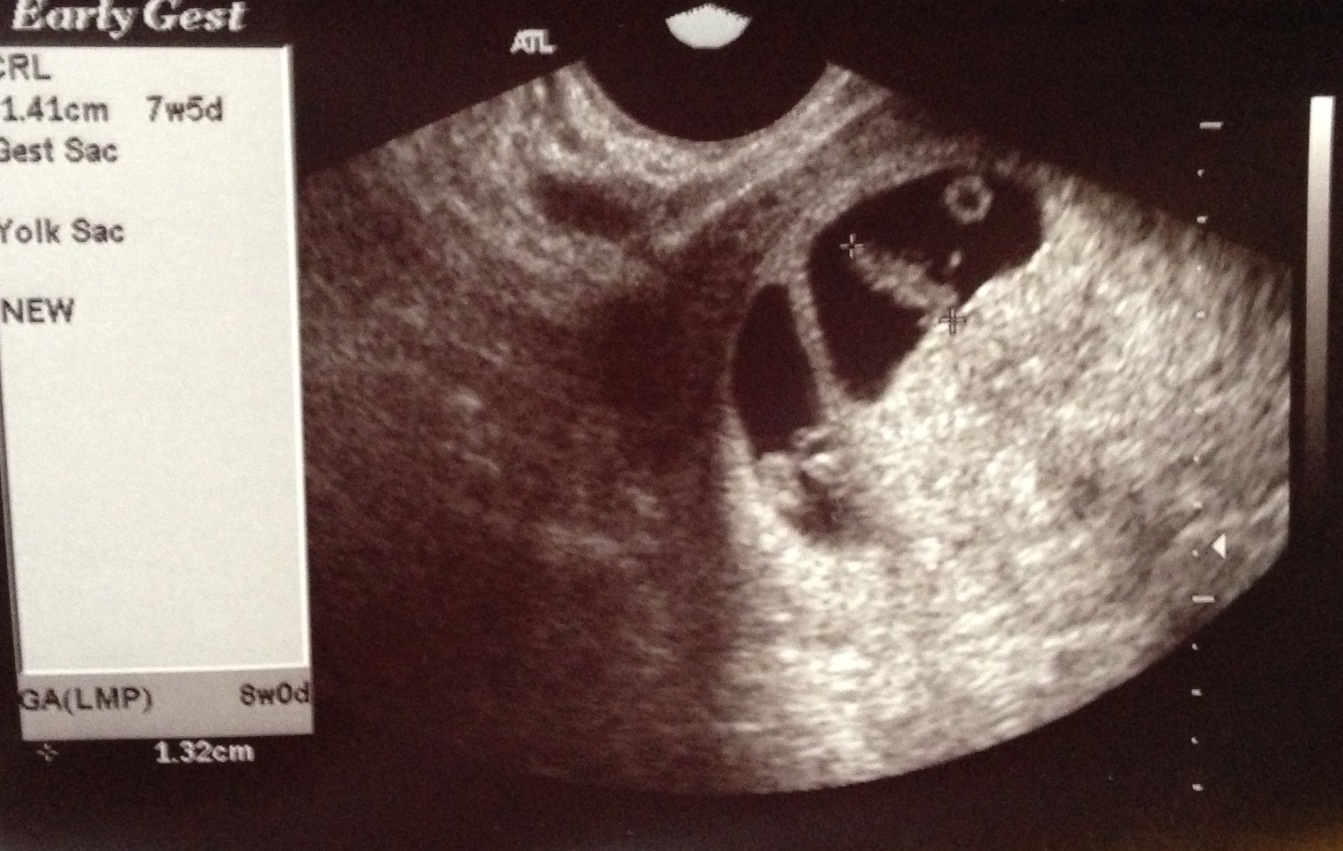

Hmmm... Could be. What I see looks like a faint second "blob" in what looks like the same sac. Here is my first ultrasound pic of my mo/di twins at 8w 6d for comparison. When are you seeing the specialist? Hopefully soon?!? Did they find a heartbeat/s? Either way, congrats in your pregnancy and good luck! :)

Eta: I guess it also looks like there could be a faint second sac off to the left? What exactly did your OB say?

• Here's my 7w5d u/s and 8w6d two clear sacs and babies...didn't matter how he moved the probe. So I'm inclined to believe you only have one sac, I'm no expert though. Good luck.